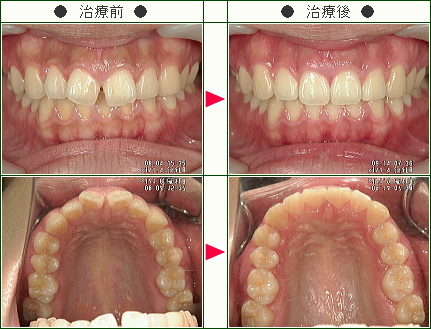

前歯のすきっ歯矯正の治療症例解説(20歳から39歳まで)--部分矯正--その2

☆前歯のすきっ歯矯正症例[ちか様 25歳 女性]